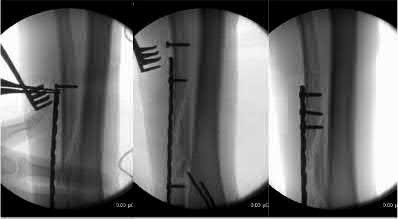

A 35 year-old female presents after prolonged extrication from a motor vehicle collision complaining of severe pelvic pain. Physical examination reveals diminished perianal sensation. She is otherwise neurologically intact. Figures A through D are radiographs and representative CT cuts of her injury. Which of the following nerve roots has likely been injured by the acute trauma?

The clinical scenario is consistent with a high-energy sacral fracture. The radiographs in figures A and B demonstrate a sacral fracture with posterior displacement of the right hemipelvis seen on the inlet view. Figures C and D are axial and sagittal CT images which show a displaced fracture of the right

hemisacrum along with a transvere fracture component through the S3 body . Diminished perianal sensation is concerning for an S2 nerve root injury.

Mehta et al reviewed the current management of sacral fractures. They note that the S1 and S2 nerve roots are more likely to be injured with sacral fractures as they occupy 1/3 to 1/4 of the neural foramina, as opposed to S3 and S4, which only occupy 1/6 of the neural foramina.

Robles reviewed the current literature to ascertain principles of evaluation and treatment for transverse sacral fractures. The author notes that injury to nerve roots S2 to S5 is manifested by impairment of urinary and anal continence and sexual function.